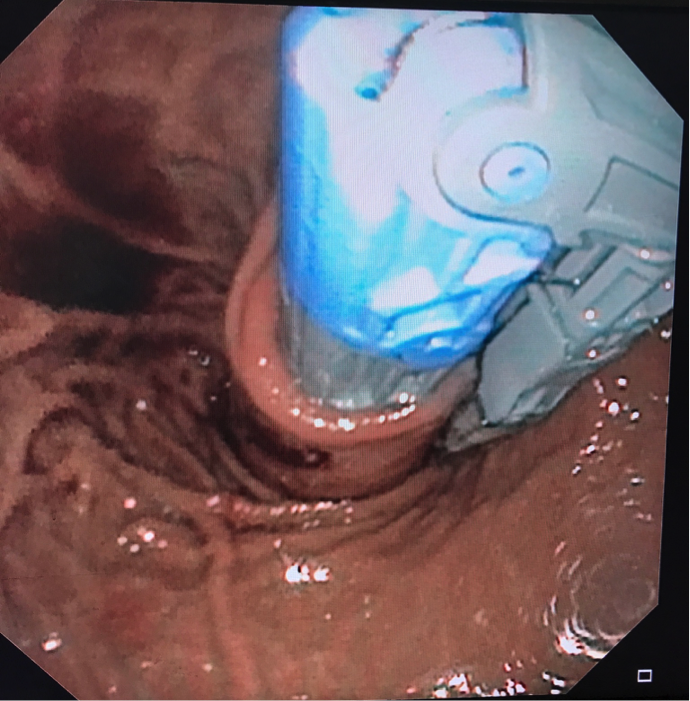

We are pleased to offer a new, exciting treatment option: transoral incisionless fundoplication (TIF). This is a procedure done entirely through the mouth, with no need for incisions. The TIF procedure reconstructs an antireflux valve at the gastroesophageal junction and reduces hiatal hernia, restoring natural anatomical geometry. The procedure generally takes less than one hour; most patients can go home the next day and return to work and most normal activities within a few days.